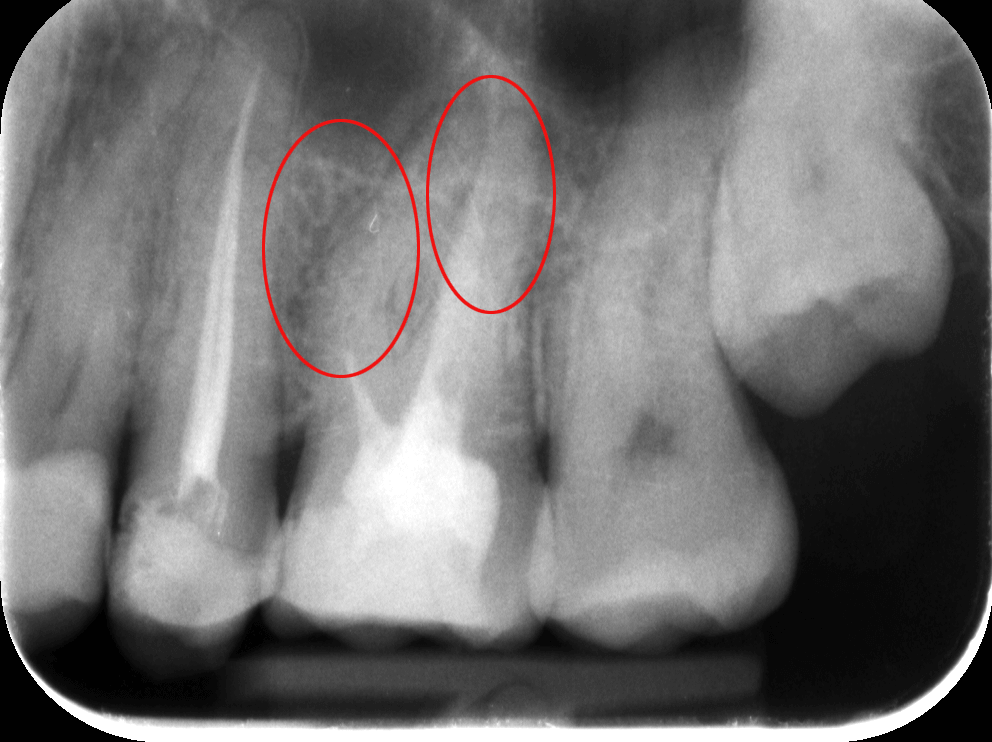

Dr. Molnár Katalin, egyik szakértőnk vizsgálta meg a pácienst. A szájüregi vizsgálatot röntgenfelvétel követte – a diagnózis felállításához és a kezelés menetének felvázolásához mindenképpen szükség van röntgenfelvételre is. A képen látható, hogy egy rosszul elvégzett gyökértömés van az egyik felső 6-osban, amely körül már látható a kezdődő elváltozás. A rossz gyökértömés körül ugyanis könnyen gyulladás alakul ki, amely nemcsak fájdalmas, de meg is változtatja a csontszövet szerkezetét.

Az elkészült röntgenfelvételeken tehát a sötétebb területek jelzik a gyulladás fennállását (pirossal bekarikáztuk), a foggyökércsatornák halványabban látszanak, elmosódottabbak vagy teljesen eltűnnek a felvételen.